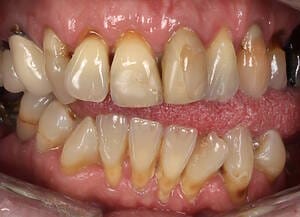

Initial Situation

Natalie arrived at Wimpole Street Dental Clinic facing an extremely challenging dental situation. She had several missing and damaged teeth, infections in the bone, and significant bite issues caused by a long-term tongue habit. On top of that, she was a smoker and had developed a strong dental phobia over the years, making it difficult for her to seek help sooner.

Her case was not straightforward, but it was clear that the right care could offer a completely new beginning. She was referred to Prof Dr Christian Mehl, a leading expert in dental implantology, who partnered with Mr George Leventi of Aion Dental to deliver a highly personalised and technically advanced treatment plan.